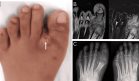

Durante el examen dermatológico, se evidenciaron placas engrosadas e hiperqueratósicas, así como lesiones verrugosas localizadas principalmente en palmas y plantas.

A nivel musculoesquelético, presentaba sinovitis bilateral, desviación cubital de ambas manos y deformidades en las articulaciones metacarpofalángicas (MCF) e interfalángicas proximales (IFP), además de compromiso en las metatarsofalángicas (MTF).

Las radiografías de manos y pies revelaron erosiones óseas periarticulares y estrechamiento del espacio articular, sin signos evidentes de osteopenia típica de la artritis reumatoide clásica.